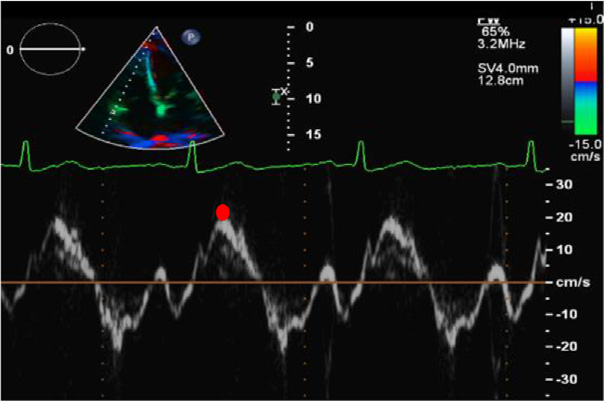

③TDI S’速度

关键点

建议

聚焦RV的A4Ch切面,沿着TV外侧环放置在RVFW基底部的TDI的4mm取样容积。该测量与角度相关,收缩轴和声束间的最大角度应<20°。TDI S’的速度定义为基以上线(红点)的峰值收缩速度。